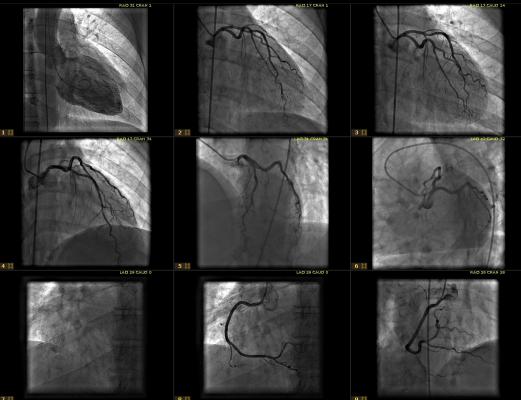

April 4, 2013 — Siemens Healthcare has introduced a new version of its cardiovascular imaging and information system. From routine to advanced readings, the new version of syngo Dynamics helps streamline workflows and optimize clinical utilization.